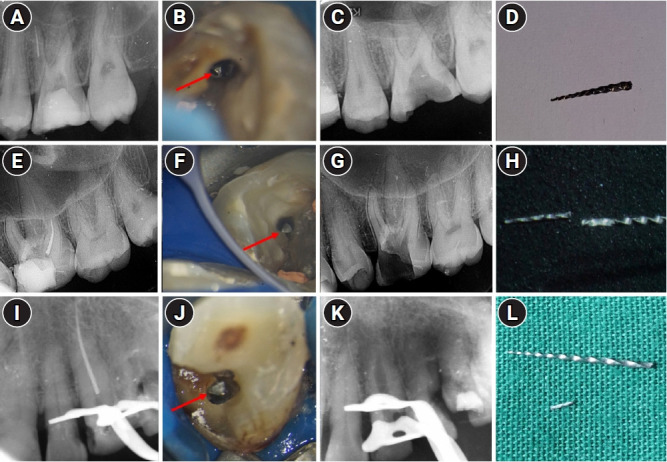

Methods: Cases referred for the management of separated endodontic instruments (SEI) from 2013 to 2023 were considered for this study. Data related to demographics, tooth type, file type, and retrieval were documented in an Excel sheet. Eight prognostic factors assumed to influence the retrieval were analyzed in this study. The secondary aim was to compare the pattern of SEI and retrievability between conventional nickel-titanium files and newer generation heat-treated nickel-titanium files. Retrieval was attempted by a senior endodontist under the dental operating microscope. Various ultrasonic tips and a Broken Tool Removal loop system were used during retrieval. Simple descriptive statistics were performed. Binomial logistic regression was done to identify the effect of the eight prognostic factors on the retrieval outcome.

Results: A total of 190 SEI was reported. SEI occurred more often in posterior teeth than anterior teeth, mandibular arch than maxillary arch, and in larger files than smaller files. Separation occurred more often in the apical third compared to the other levels. Retrieval was attempted in 88 cases and successful in 70 cases (79.5%). The larger taper and apical position of the SEI negatively influenced the retrieval by 1.4 and 8.7 times, respectively.

Conclusions: Retrieval of SEI was successful in the majority of the cases. An increase in taper and apically placed SEI negatively impacted the retrieval. There was no difference in the pattern of separation nor retrievability between conventional nickel-titanium files and newer generation heat-treated nickel-titanium files.